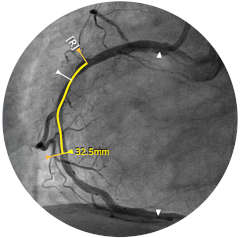

A medida que aumenta el número de pacientes cardiovasculares y vasculares, también lo hace la necesidad de trabajar de forma más inteligente y rápida. Philips IntraSight le ofrece estas herramientas intervencionistas, las mejores de su clase, que le permiten ver con claridad para poder tomar decisiones clínicas rápidas e informadas que pueden conducir a planes de tratamiento óptimos. La integración de la más avanzada plataforma de fisiología e imagenología en su flujo de trabajo debe ser inteligente, sencilla y constante. IntraSight es la única plataforma intervencionista que: Para los clientes con suites intervencionistas que no son de Philips, IntraSight 7 ofrece una integración constante y un uso completo de nuestras aplicaciones de intervención. IntraSight 7 promueve una gestión mejorada del flujo de trabajo con el módulo de pantalla táctil junto a la mesa que permite la facilidad de uso y el acceso a las mejores herramientas intervencionistas de su clase, como iFR/FFR, IVUS y el corregistro. Además, la integración de IntraSight 7 con las suites intervencionistas que no son de Philips permite a los clientes beneficiarse de soluciones intuitivas como, por ejemplo, la mejora de los vasos y la detección de dispositivos, lo que, en última instancia, permite a todos los clientes beneficiarse de la oferta integral de soluciones inteligentes de IntraSight 7 sin compromiso.

Presentamos la nueva plataforma de aplicaciones intervencionistas Philips IntraSight, en la que la imagen, la fisiología, el corregistro* y el software se unen para facilitar una atención óptima del paciente. IntraSight ofrece un conjunto completo de modalidades clínicamente probadas, como la iFR/FFR, la IVUS y el corregistro* para simplificar las intervenciones complejas, acelerar los procedimientos rutinarios y proporcionar una mejor atención al paciente.

Construida sobre una plataforma inteligente basada en aplicaciones que puede escalar para satisfacer las necesidades cambiantes de su laboratorio cuando se disponga de nuevas aplicaciones o modalidades, sin necesidad de adquirir nuevo hardware. Solo Philips IntraSight ofrece las mejores herramientas de imagenología y fisiología de su clase con iFR, corregistro iFR*, FFR, IVUS, corregistro IVUS* y Angio+*. Con su arquitectura modular, IntraSight se mantiene a la vanguardia de los últimos avances y actualizaciones de seguridad importantes.

Orientación IVUS

es "definitivamente beneficiosa" para los pacientes, y dio lugar a un cambio de los planes de tratamiento el 74% de las veces 1,6,7